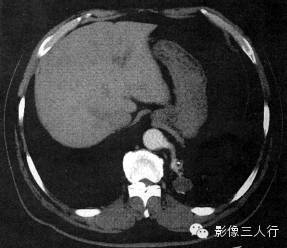

报告书写:扫描显示胸廓对称,左肺下叶脊柱旁见团块样病变,其内可见囊状空腔。双侧肺门不大,纵隔居中,其内未见肿大的淋巴结。心脏大小正常,胸壁软组织未见异常。增强及三维重建显示供应血管来自腹主动脉(图2)。

图2肺叶外型肺隔离症

(A)平扫

(B)增强扫描